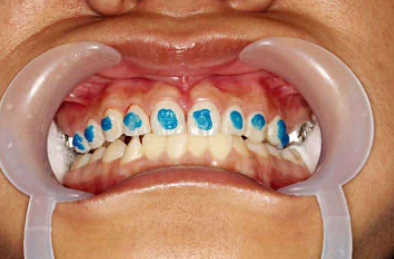

下颌粘托槽的时候,如果上颌牙尖咬到了下颌托槽上,可以在上颌磨牙工作尖的工作面做蓝色树脂颌垫(图10)。